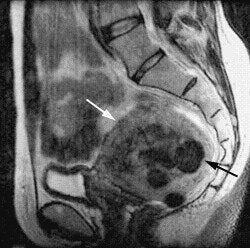

![]() |

| This pre-embolization, sagittal T1-weighted midline MR depicts an enlarged uterus with multiple fibroids highlighted by white arrows. The black arrow points out the uterus impinging anteriorly on the bladder neck. Image courtesy of Dr. Steven Janney Smith. |